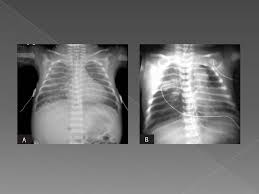

Atypical Pneumonia Radiology Reference Article Radiopaedia Org

Atypical Pneumonia Radiology Reference Article Radiopaedia Org from prod-images-static.radiopaedia.org